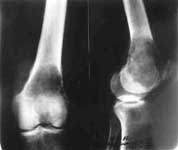

1.Опухоль нижней трети бедра.

2.Удаление опухоли.

3.Замещение дефекта бедра.

4.В процессе замещения.

5.Результат лечения.